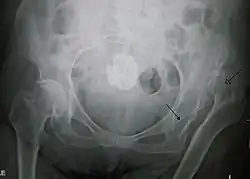

X-ray showing a joint dislocation of the left hip.

Dislocation of the left hip, secondary to developmental hip dysplasia. Closed arrow marks the acetabulum, open arrow the femoral head.